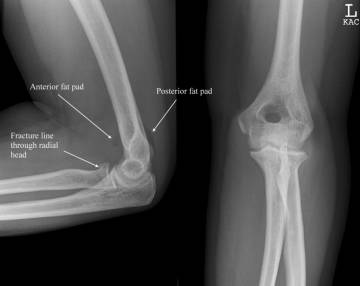

Essex-Lopresti骨折

桡骨颈骨折伴有远端尺桡关节分离。